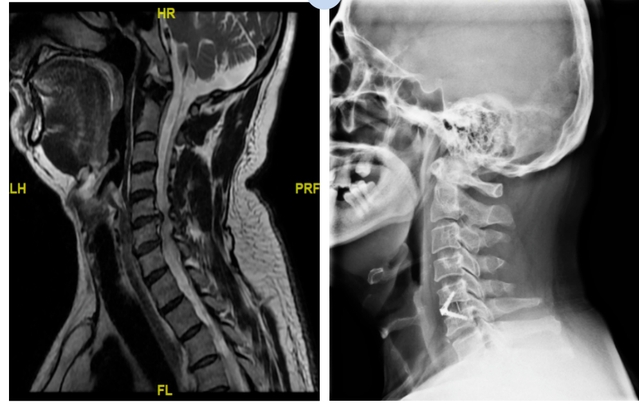

●一位患者被颈椎病困扰多年,颈椎长期不稳定且合并椎间盘突出,椎体后缘增生,韧带骨化,导致突出物的硬度很高,就像一块“石头”压迫脊髓,再不处理,将造成更加严重的后果。

颈椎手术毗邻关系复杂,伴有重要的神经血管等,从技术上需要医生具备精准的解剖结构专业知识和丰富的临床手术经验,手术难度大且风险系数高。金沙娱乐城app 骨科主任言湛军组织协调骨科、麻醉科、医学影像科等科室,详细评估患者的情况,明确诊断并制定手术方案,最后决定为两位患者开展颈椎前路椎管减压、椎间融合内固定手术,通过微创治疗将突出物彻底切除。

术后患者椎间隙高度恢复,生理曲度恢复,神经受压解除;头部胀痛,右上肢放射痛得到缓解。

巨大的突出物已切除,椎间隙高度恢复,椎管容积扩大,神经压迫解除,双手麻木感消失。